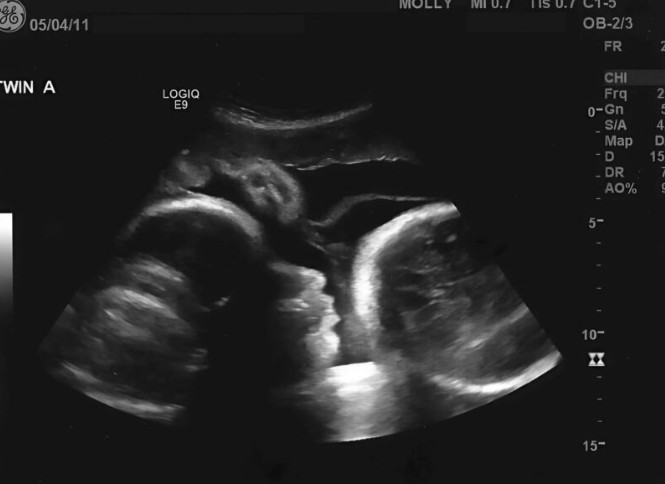

Na kraju, Larisa je shvatila da je vrijeme da posjeti ginekologa. U njenoj glavi, to je bila formalnost — konačna potvrda njene trudnoće. No, pregled je otkrio nešto sasvim drugačije. Na ekranu nije bila beba, već ozbiljna medicinska stanja koja su uzrokovala povećanje njenog stomaka. Ovaj trenutak je bio šokantan — suočila se s istinom koja je potpuno promijenila njen život. Dok je doktor objašnjavao dijagnozu, Larisa je osjećala kako joj se cijeli svijet ruši. Ono čemu se nadala, ispostavilo se kao daleko od stvarnosti, a njene želje su se srušile kao kula od karata. To je bio trenutak kada je počela shvatati ozbiljnost situacije, a njena emocionalna stanja su postala kompleksna — od gubitka nade do straha od nepoznatog.